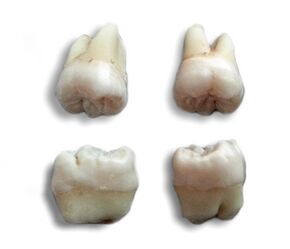

Weisheitszähne-1.jpg

Wisdom teeth

Morphology of wisdom teeth can be variable.

Maxillary (upper) third molars commonly have a triangular crown with a deep central fossa from which multiple irregular fissures originate. Their roots are commonly fused together and can be irregular in shape.

Mandibular (lower) third molars are the smallest molar teeth in the permanent dentition. The crown usually takes on a rounded rectangular shape that features four or five cusps with an irregular fissure pattern. Roots are greatly reduced in size and can be fused together.[8]